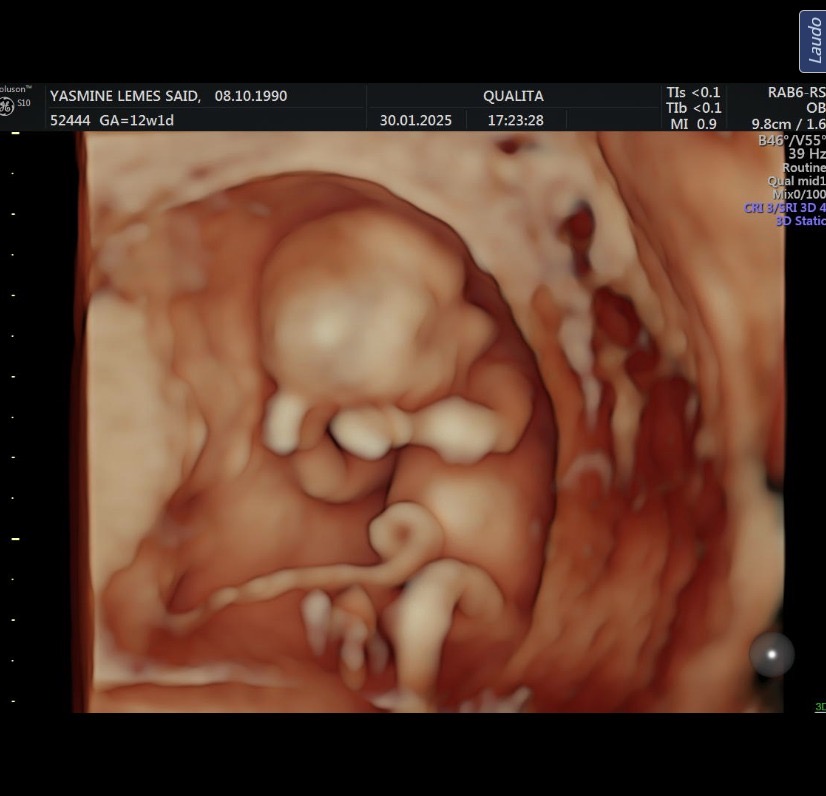

Object 6e150fcb-8112-442c-9c1a-c185a7a6ef1c.jpeg